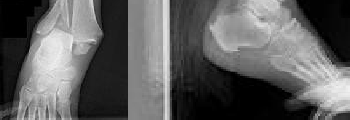

A 24-year-old football player sustains a high-energy hyperplantarflexion injury to his midfoot. Weight-bearing radiographs suggest a subtle Lisfranc injury. Which of the following anatomic descriptions accurately characterizes the primary strong band of the Lisfranc ligament complex?

Correct Answer: It connects the medial cuneiform to the base of the second metatarsal

Explanation:

The Lisfranc ligament is an oblique, interosseous ligament that originates on the lateral aspect of the medial cuneiform and inserts on the medial aspect of the base of the second metatarsal. It is critical for midfoot stability because there is no direct intermetatarsal ligamentous connection between the bases of the first and second metatarsals.